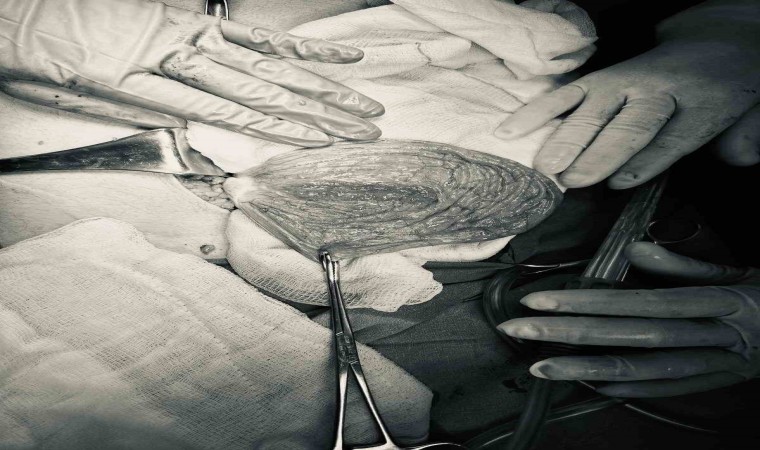

Sivas’ta yaşayan 12 yaşındaki N.B. şiddetli karın ağrıları ve düzensiz adet kanamaları şikayetiyle hastaneye başvurdu. Yapılan detaylı tetkikler sonucunda genç kızın karın bölgesinde yaklaşık 25 santimetre çapında adeta kavun büyüklüğünde bir kist olduğu tespit edildi. Medicana Sivas Hastanesi’nde Çocuk Cerrahisi Uzmanı Op. Dr. Mahmut Aluç tarafından gerçekleştirilen başarılı bir operasyonla, genç kızın sol yumurtalığında bulunan ve karaciğere kadar uzanan devasa kist içerisindeki 1.6 litre su boşaltılıp, başarıyla çıkarıldı. Sağlığına kavuşan genç kız taburcu edildi.

Çocuk Cerrahisi Uzmanı Op. Dr. Mahmut Aluç, kisttin içerisinden yaklaşık 1.6 litre sıvı boşaltıldığını söyleyerek, “ Karın ağrısı, düzensiz adet şikayetiyle bize geldi. Dışarıda yapan tetkiklerde ve bizde yapılan tetkiklerinde karın içerisinde yaklaşık yirmi beş santimetrelik çapında bir kitli kitle tespit ettik. Burada da tetkiklerimize tekrar baktığımızda sol över kökenli bir kisttik yapı olduğunun farkına vardık. Gerekli incelemeleri yaptıktan sonra ve ailenin onayını aldıktan sonra hastayı operasyona aldık. Karaciğere kadar uzanan bir kisttik yapımız vardı. Onun içerisinde yaklaşık 1.6 litre sıvı boşalttık. Over dokusunu, yumurtalık dokusunu koruyarak kisti tamamen eksize ettik. Hastamızı şifayla taburcu ettik. Patoloji sonucumuz da iyi huylu olarak geldi” dedi.